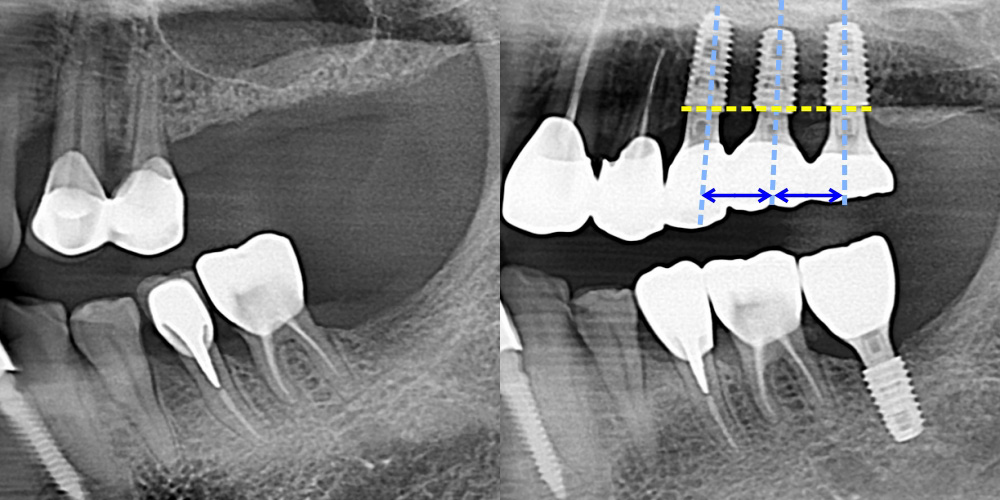

가이드 임플란트로 정확한 위치에 식립

임플란트의 위치·각도·깊이를 사방에서 잡아주는

환자 맞춤형 가이드 장치를 사용합니다.

계획한 그대로 정확한 위치, 각도, 간격으로 임플란트를 식립합니다.

0.2mm 까지 컨트롤하는 차원이 다른 정확함

달걀껍질 두께인 약 0.2mm까지 조절해서 식립하는 차원이 다른 정확함

전체 임플란트, 다수 임플란트에서 좋습니다.

심어야될 임플란트 숫자가 많으면

정확한 위치에 심기가 더 어렵습니다.

가이드 임플란트를 사용하면  여러 개를

동시에 식립할 때도 정확한 식립이 가능합니다.